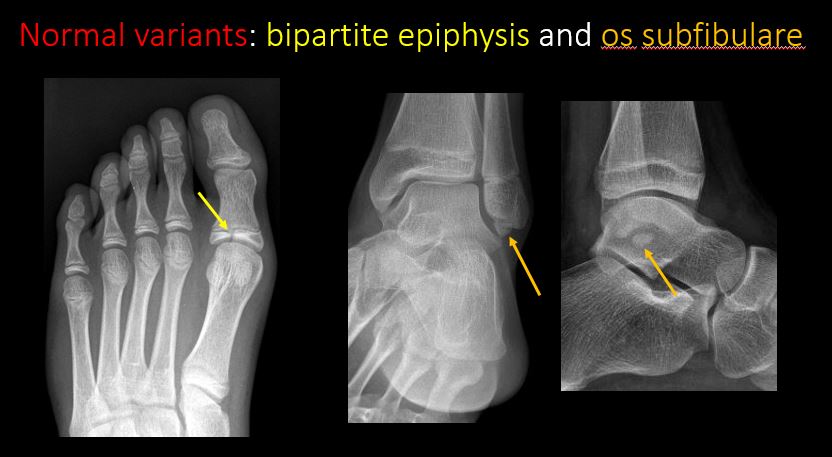

There are developmental changes or other anatomic variants or other existing conditions that may or may not be contributing to symptoms which can or should be further evaluated non-emergently or are otherwise incidental. [Yes/No]